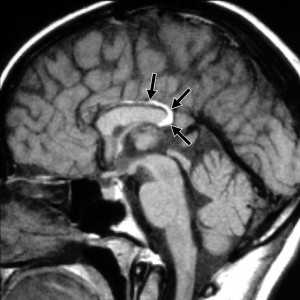

Липома представляет собой скопление в субарахноидальном пространстве зачаточных жировых клеток с примесью коллагена. Происходят липомы из остатков примитивной эмбриональной оболочки. Эта мальформация оболочек мозга связана с нарушением дифференцировки мезенхимы на мягкую мозговую оболочку и субарахноидальное пространство. Частота липомы составляет менее 0.5% от внутричерепных образований. Обычно липомы локализуется в мозолистом теле, в межполушарной щели, воронке гипофиза и гипоталамусе, реже вокруг червя мозжечка и пластины четверохолмия и мосто-мозжечковом углу и Липомы мозолистого тела сочетаются с его агенезией и в 60% случаев с распространением на сосудистое сплетение. При МРТ головного мозга липома четко очерчена, без отека вокруг и масс-эффекта, кость не разрушает. Структура образования чаще однородная, жировой интенсивности сигнала - то есть выраженно гиперинтенсивная на Т1-взвешенных МРТ и немного менее интенсивная по отношению к ликвору на Т2-взвешенных МРТ. Иногда встречаются неоднородные липомы с участками низкого сигнала от кальцинатов и сосудов, проходящих ее насквозь. При сомнениях в диагнозе надо выполнить МРТ головного мозга с подавлением жира или можно сделать КТ. На КТ липома всегда резко гиподенсна и может содержать включения кальция.

МРТ головного мозга. Сагиттальная Т1-взвешенная МРТ. Липома мозолистого тела.